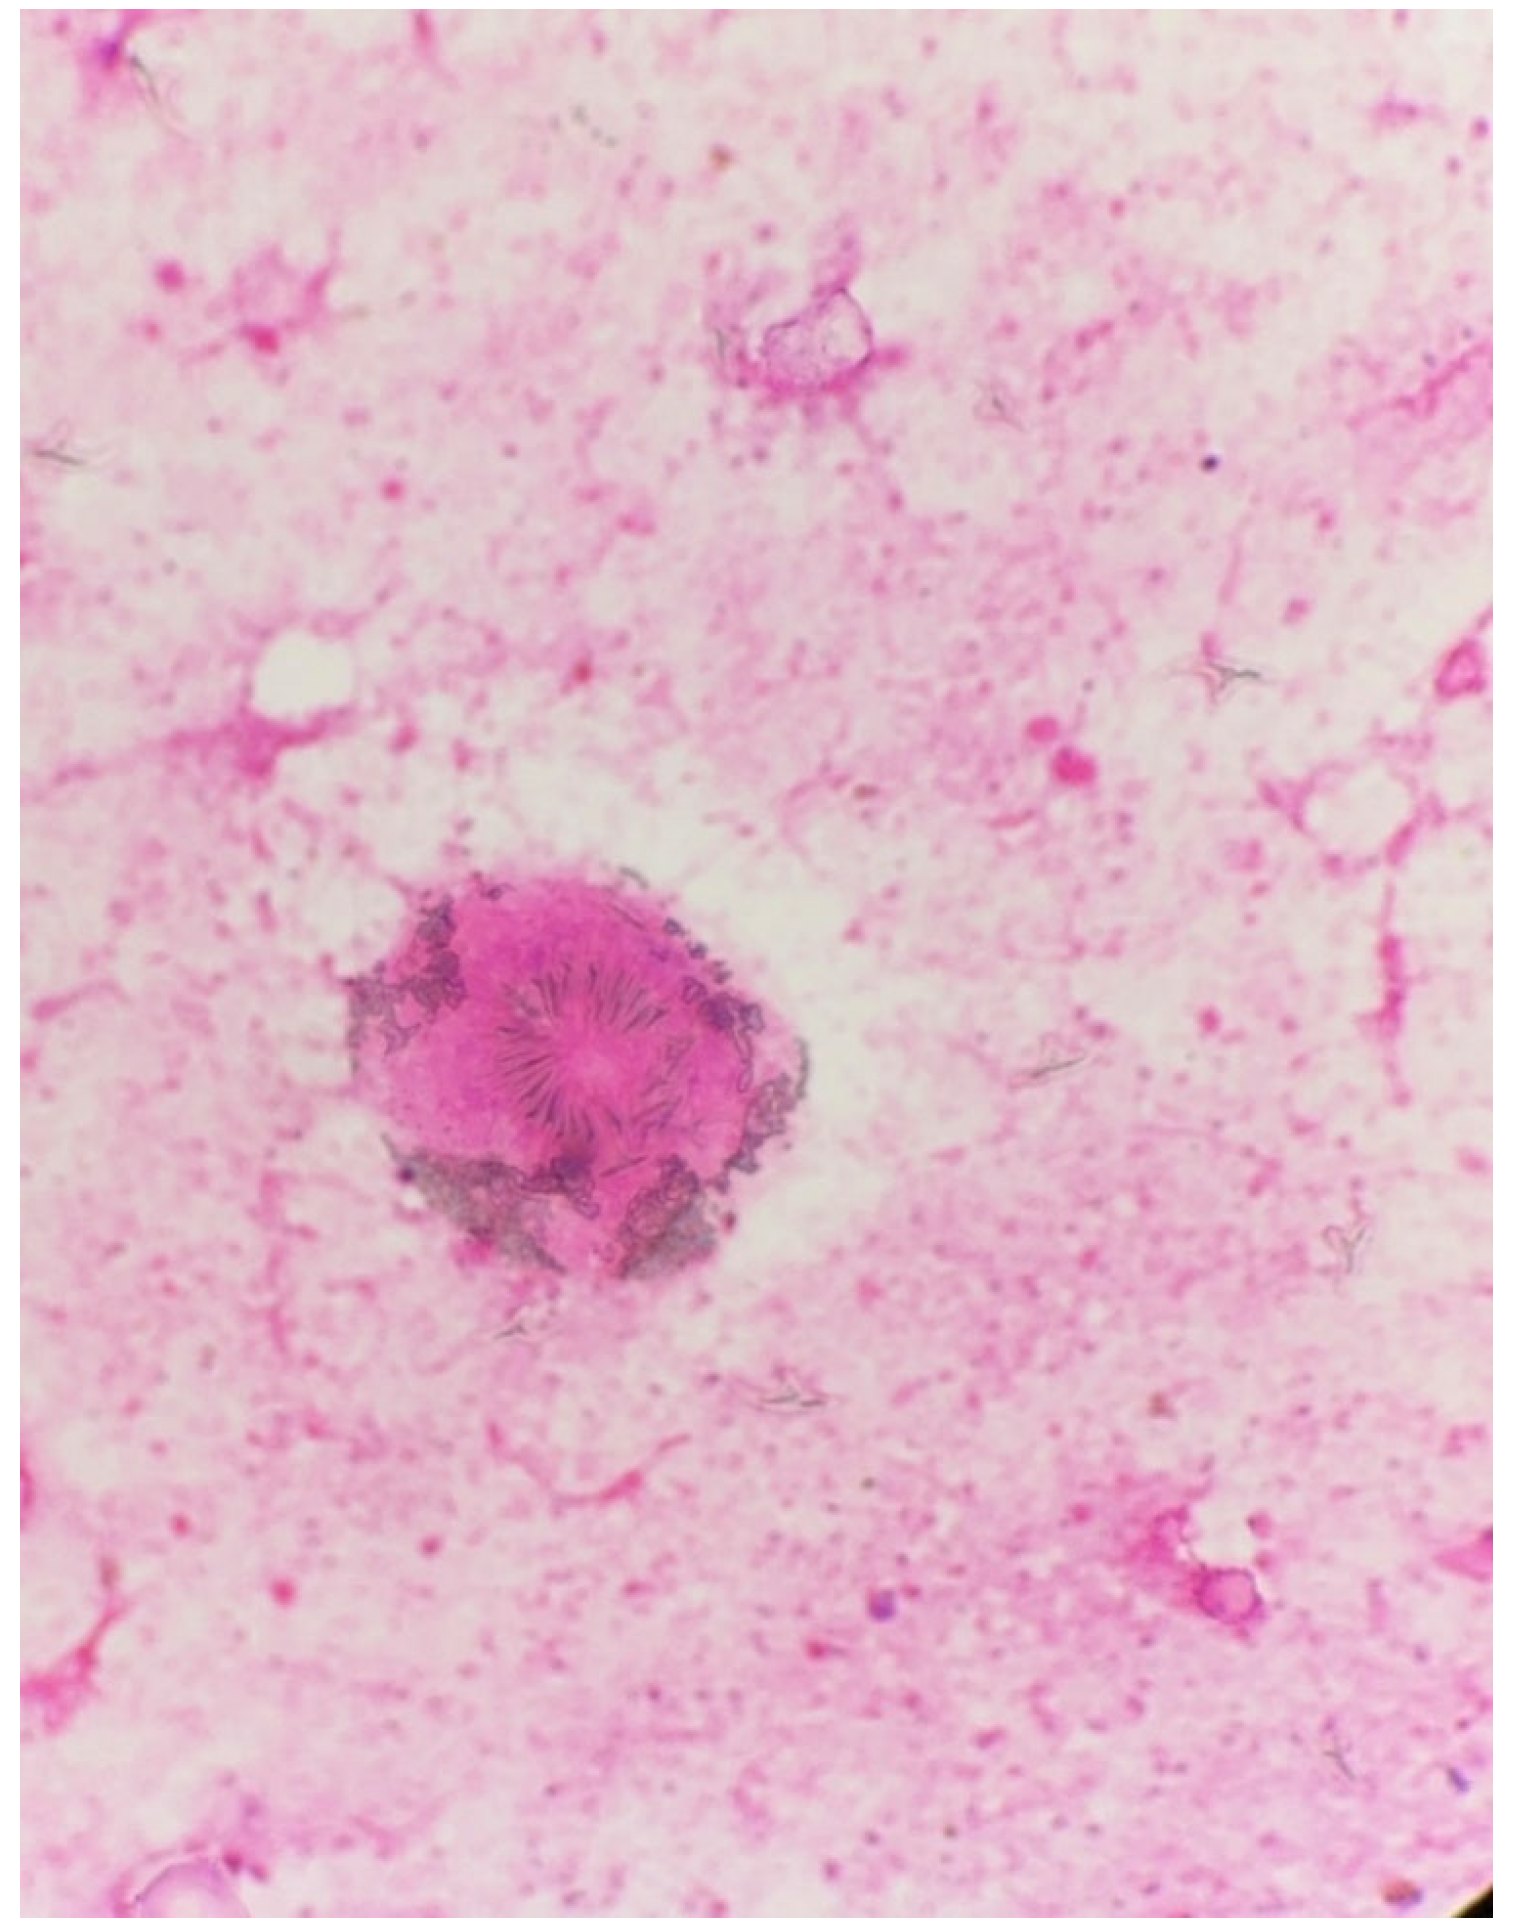

The material was submitted to intraoperative examination (Figure 3). The cyst measured (ex vivo) 95 mm × 61 mm × 22 mm (Figure 4). The dimensions of the postoperative specimen are the ex vivo dimensions after removal and dissection of the cyst. The cyst flattened after fluid removal, explaining the difference in dimensions compared to the CT scan, which showed the cyst in situ, filled with fluid. Upon dissection, it had an uneven whitish internal surface with nodular thickening. Biopsies were collected for histological and cytological examination. The cyst fluid had not previously been aspirated for independent analysis. Cytological examination involved making a smear from the inner surface of the cyst wall, but only biopsies from the cyst wall, not from the nodular portion, were collected for histological examination. The cyst wall showed signs of necrosis and the presence of histiocytes and lymphoid cells. Cytological examination revealed structures consistent with protoscolex (Figure 5), suggesting Echinococcus spp.

The material was fixed in formalin to prepare hematoxylin and eosin (H&E)-stained slides. Dissection of the cyst caused the liquid filling it to spill over its surface and may have contained numerous protoscolices, the so-called hydatide sand. We took samples from both the nodular lesion and the cyst wall. In both of these locations, protoscolices were visible under the microscope after H&E staining, but there were more of them in the sections from the nodular lesion. However, whether the protoscolices were transferred from one location to another due to the dissection of the cyst cannot be determined. Because only a few protoscolex were found in the nodular lesion, it appears to be the result of contamination of this area. However, this is hypothetical. Therefore, differentiating between viable daughter cysts and reactive secondarily seeded tissue in the nodular lesion is problematic. The slides revealed a cyst wall composed of a germinal (inner) layer and an outer layer with a 0.40-mm-thick concentrically arranged acellular layer of lamellae (Figure 6). The outer layer was surrounded by a pericyst, a fibrous capsule resulting from the host response (i.e., not part of the parasitic tissues). The pericyst was up to 2.2-mm-thick and contained clusters of histiocytes, macrophages, and inflammatory cells [Figure 6] The examined slides also revealed numerous protoscolices with hooklet rings and suckers (Figure 6), free hooklets (Figure 6), and a brood capsule containing protoscolices, which are produced by the germinal membrane (Figure 6). This image was consistent with the diagnosis of a E. granulosus cyst.

Figure 5. Intraoperative light microscopy images showing the viable protoscolex of Echinococcus spp. stained with H&E (40×).